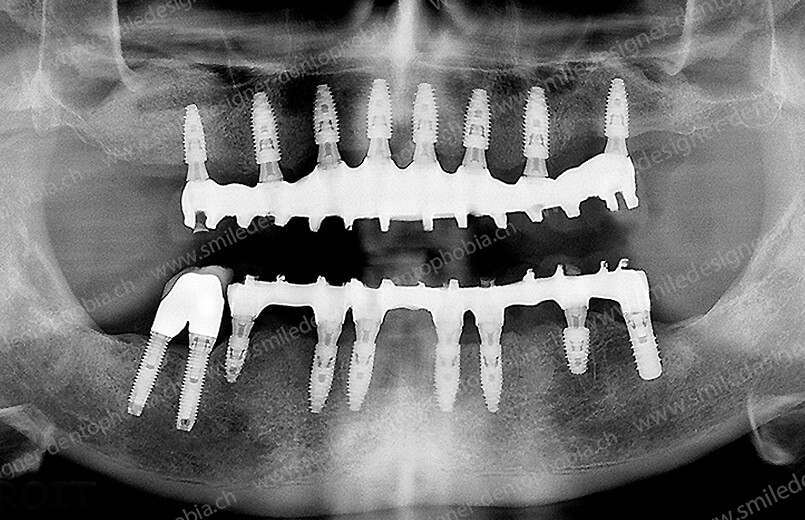

Cas clinique « DOMINO SURGERIES MCI » : Bridge implanto-porté sans extension postérieure (ALL ON 10/8). Version définitive des bridges avec un cosmétique en céramique. Double comblements de sinus et double greffes osseuses d’apposition pour la reconstruction du maxillaire.

Cas clinique « DOMINO SURGERIES MCI » : Bridge implanto-porté sans extension postérieure (ALL ON 8/6). Version définitive des bridges avec un cosmétique en céramique. Double comblements de sinus et double greffes osseuses d’apposition pour la reconstruction du maxillaire.

Version définitive des bridges avec un cosmétique en céramique (ALL ON 10/6). Double comblements de sinus et double greffes osseuses d’apposition pour la reconstruction du maxillaire.

- Résultat final : une arcade dentaire complète, de molaire à molaire, avec des bridges en céramique, pour une mastication optimale et un sourire naturel.